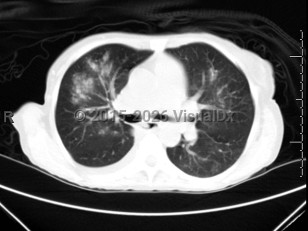

EVALI

COVID-19

Drug-induced pneumonitis